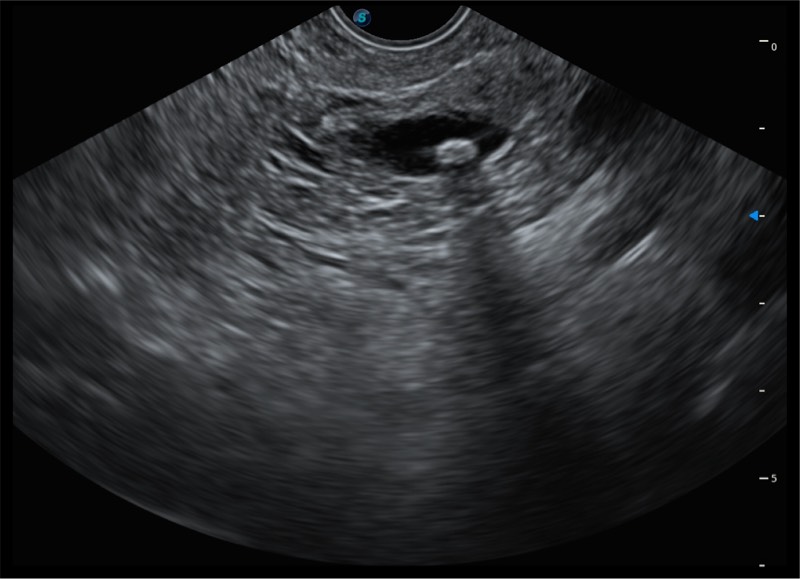

搭载百万级CMOS成像技术

及自主研发凸阵换能器,

可呈现优质的内镜和超声画面

基于二十年的超声技术积累,亚星官网提供了最新一代的独立超声主机,在提供高质量图像的同时满足多学科使用。具备常见多普勒技术并提供弹性成像、声学造影等高端影像技术。新一代传感器具有更强的抗干扰能力并减少图像伪影。

4-12MHZ宽频输出